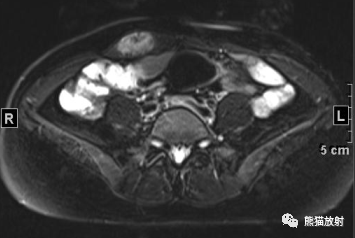

女41岁,腹壁肿物。

最后诊断: 韧带样纤维瘤

韧带样型纤维瘤病

5、DTF信号特点及其不均匀性与病灶内组织学成分的比例和分布有关:细胞成分多的区域T2WI信号较高,胶原纤维多的区域T2WI信号较低;

6、病灶内各序列见条带状低信号影,无明显强化,病理为致密胶原纤维化和少细胞区,是 DTF较特征性的表现。